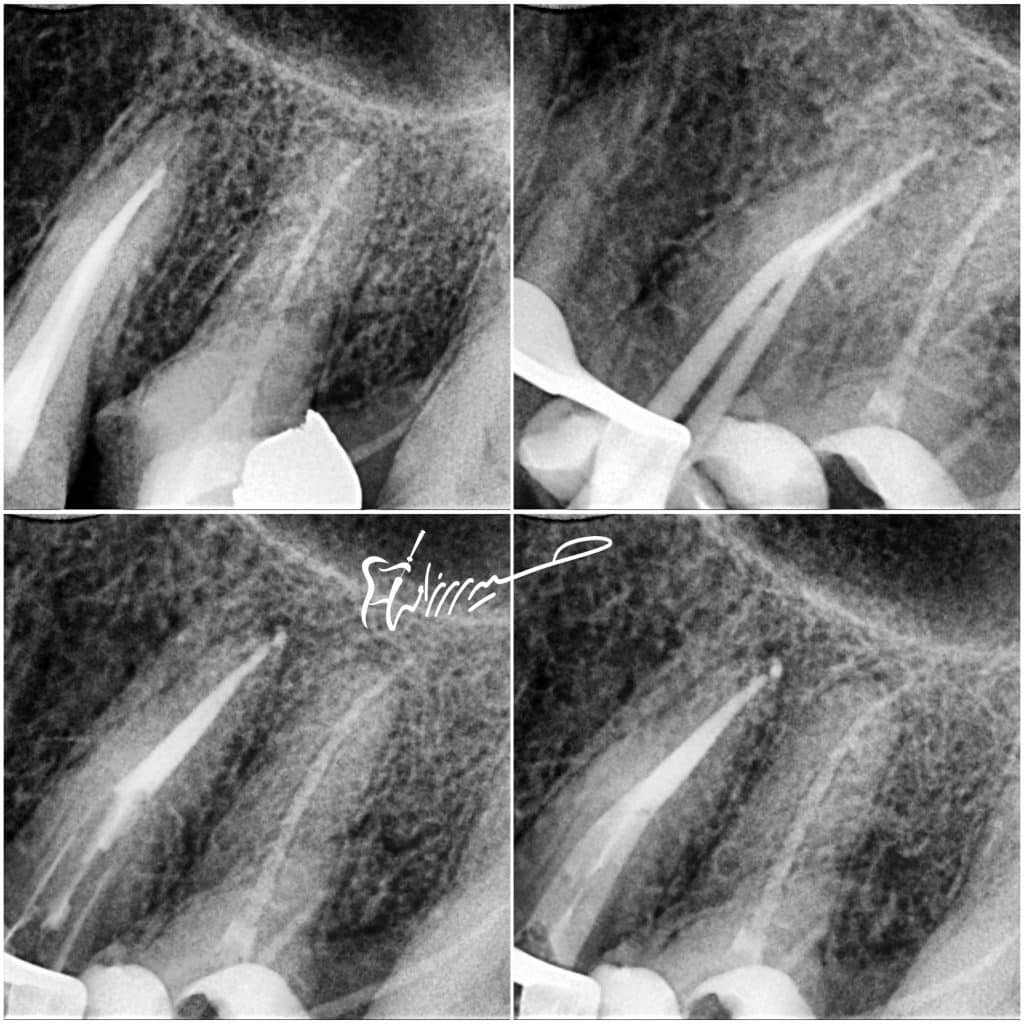

Bad RCT need re treatment

deep margin must elevate

destructive structures and there is no feruule